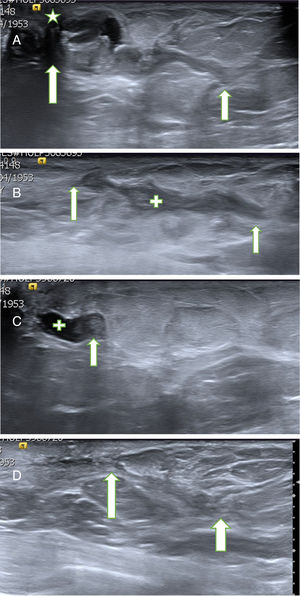

La mayor parte de los PB se diagnostican mediante ecografía2,3. Pueden presentar hallazgos ecográficos muy característicos (fig. 1A y B). En ocasiones son nódulos similares a los fibroadenomas y con menos frecuencia son lesiones sospechosas de malignidad (fig. 2 A)4,5.

A. Probable papiloma benigno (PB). Hallazgo ecográfico más frecuente y característico de PB. Paciente de 43 años con secreción uniorificial de mama izquierda. En la ecografía se apreció una lesión ecogénica con flujo doppler-color (flechas blancas) en el interior de un ducto dilatado (estructura tubular anecoica) que se correspondía con el ducto secretor, cercano al pezón (estrella). Hallazgo BIRADS 3. La BAV confirmó el diagnóstico de PB. B. Probable PB intraquístico. Hallazgo ecográfico poco frecuente pero característico de PB. Paciente de 53 años que acudió por nódulo palpable periareolar de mama derecha. La ecografía mostró una lesión quística con contenido espeso (estrella azul) sobre líquido menos espeso, anecoico (estrella blanca). En la pared superior del quiste se apreció un nódulo ecogénico con flujo doppler-color (sólido), característico de un PB intraquístico (flecha azul). Hallazgo BIRADS 3. La BAV confirmó el diagnóstico de PB.

A. Probable PB. Paciente de 60 años con secreción uniorificial por el pezón izquierdo. La ecografía mostró un probable PB de 29mm de longitud (flechas blancas), cercano al pezón (estrella). Se extirpó con BAV, obteniendo el resultado de PB. B. Cicatriz post-BAV. En el control ecográfico al mes se apreció un área lineal hipoecogénica de contornos irregulares (cruz, limitada por las 2 flechas), relacionada con la cicatriz en evolución. No se objetivaron lesiones residuales. C. PB recidivante. El control ecográfico a los 22 meses mostró un nódulo sólido de 4mm (flecha) en el interior de un ducto dilatado (cruz), congruente con un probable PB recidivante. La paciente permanecía asintomática, ya que la secreción cedió después de la BAV. Se realizó una BAV de rescate y se confirmó el diagnóstico de PB. D. Control ecográfico a los 30 meses. La ecografía mostró un área lineal ecogénica de contornos irregulares (limitada por las 2 flechas), relacionada con la cicatriz de las 2 BAV previas, sin signos de papiloma residual.